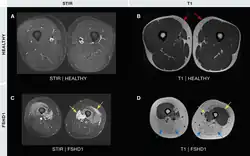

Examples of MRI imaging in FSHD. The white within the muscles of the STIR (T2) image represents muscle edema. The white within the muscles of the T1 images represents fatty infiltration.

Medical imaging (CT and MRI) have shown muscle involvement not readily apparent otherwise[37]

• Magnetic resonance imaging (MRI) is sensitive for detecting muscle damage, even in mild cases. T1-weighted MRI imaging can visualize fatty infiltration of muscles, and T2-weighted MRI imaging can visualize muscle edema. MRI can help differentiate FSHD from other muscle diseases based on the pattern of muscles involved, directing genetic testing.[37][38]